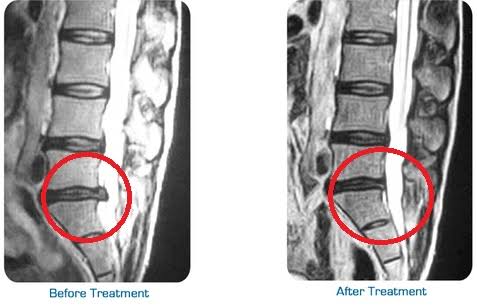

With advanced Chiropractic Adjustment techniques and Varmam Manipulation balancing techniques most of the spine related issues L4 L5 S1 disc buldge, Scoliosis, sciatica, Leg pain, knee Pain, lower Back pain, neck and Shoulder pain can be resolved with ease without Surgery avoiding further complication.